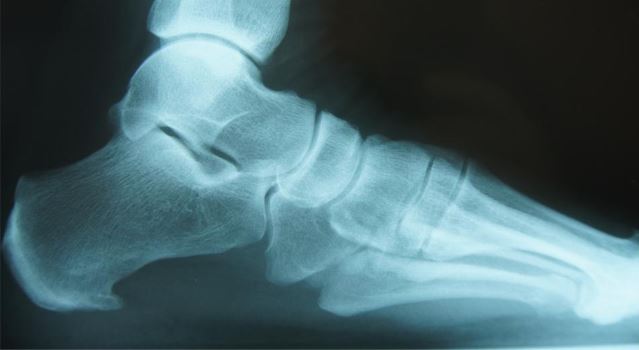

Η άκανθα είναι η οστέινη ανάπτυξη στο κάτω μέρος του οστού της πτέρνας, εκεί όπου προσφύεται η πελματιαία απονεύρωση που στην ακτινογραφία φαίνεται σαν μυτερό αγκάθι.